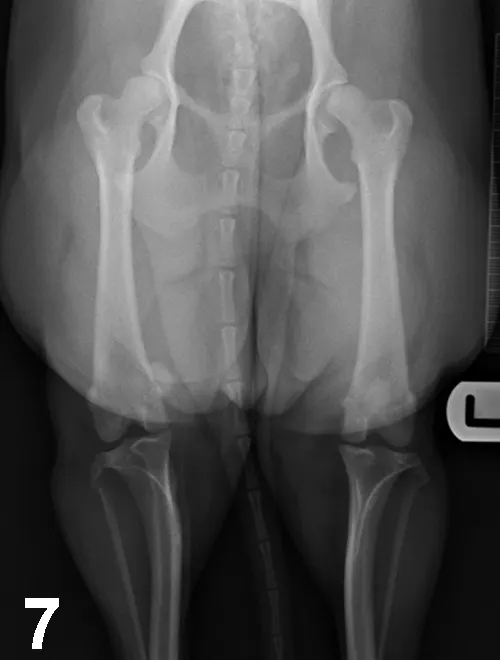

With this developmental disease, coxa vara (ie, decreased angle of inclination of the femoral head) and diminished anteversion angle (ie, less cranially oriented) of the femoral head result in medial displacement of the quadriceps mechanism. This muscular displacement results in abnormal forces that predispose the patella to luxate medially (Figure 7). MPL (95% of cases) is more common than lateral patellar luxation (LPL; 5% of cases); MPL especially affects small-breed dogs, although large-breed dogs may also be affected.1 Patellar luxation can be graded from 1 to 4, depending on the frequency of luxation and difficulty of manual reduction.

Figure 7.

Ventrodorsal radiograph of the pelvis and hindlimbs in a 12-month-old Cavalier King Charles spaniel with MPL of the right stifle. Internal rotation of the tibial tuberosity is evident.